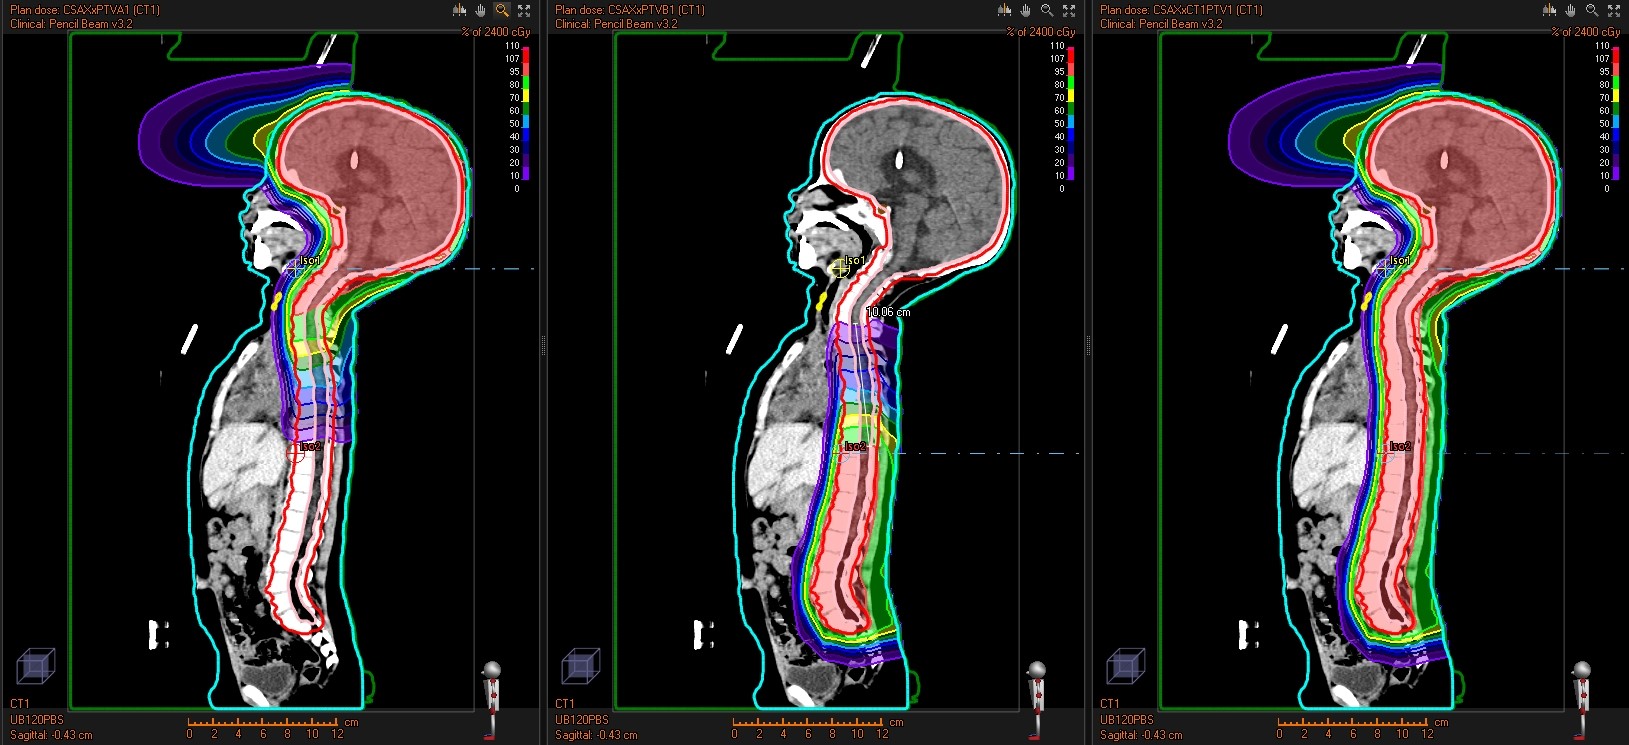

- Treatment Planning & Plan Checks: Remote IMPT and SBRT planning support and independent plan quality review.